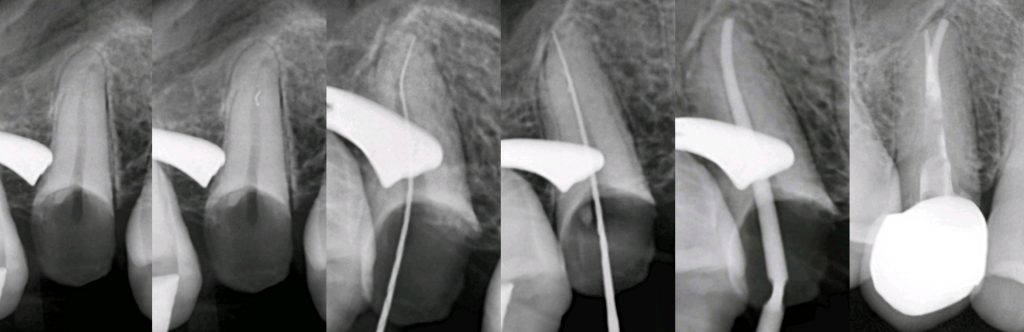

for the treatment plan, firstly we decided to focus on chief complain and perform a root canal treatment (the tooth had one root canal with very deep apical split which is challenging ) but we successfully shaped ,cleaned and filled it using CLC with bioceramic sealer.

Then we made a fiber post .

Finally, we made a horizontal prep to receive a zirconium crown with the same characteristics and brown stains that were present in the adjacent teeth.